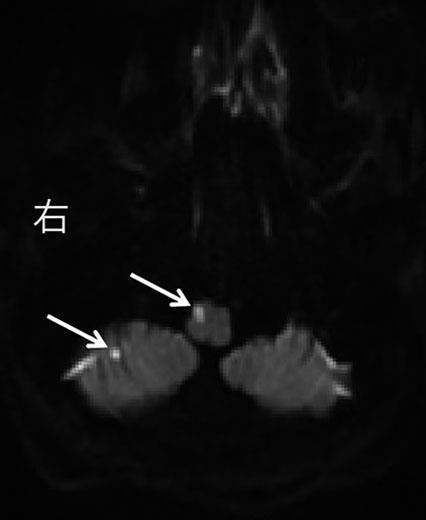

• 舞蹈症-棘红细胞增多症的早期识别和筛查

摘要:目的 探讨舞蹈症-棘红细胞增多症(chorea-acanthocytosis,ChAc)临床特点,为该病早期诊断提供思路和方法。方法 通过回顾性研究,总结ChAc临床特点。结果 符合舞蹈样运动障碍的患者中,ChAc占29%,确诊时间中位值为5.5年。患者的发病年龄为(33.57±12.23)岁;7例(100%)均有口腔运动障碍,4例(57%)出现癫痫(全面强直阵挛发作),6例(86%)出现腱反射减弱或消失,5例(71%)肌酸激酶增高;头颅磁共振可见尾状核尤其尾状核头(57%)和豆状核(29%)萎缩,侧脑室前角扩大(57%);正电子发射断层显像(positron emission tomography,PET)-电子计算机断层扫描(computed tomography,CT)可见双侧基底节区低代谢表现(43%)。所有患者均可见棘红细胞比例大于3%,基因测序29%可发现责任基因VPS13A突变。结论 ChAc的确诊时间长,口腔运动障碍、肌酸激酶增高有助于尽早识别。建议舞蹈症患者常规进行2次以上的外周血涂片,进而再进行基因检测确立诊断。